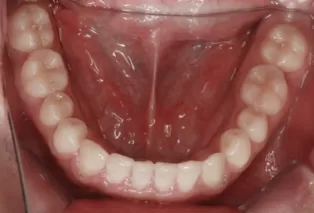

Photos intra-orales